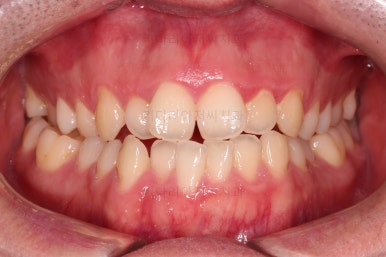

초진 시 입안의 모습입니다.

교합이 많이 안좋습니다.

위아랫니가 서로 엇갈려 가며 지그재그로 껴 들어가야 어금니 맞물림이 생기는데요.

이번 환자분은 아랫니, 아래턱이 전반적으로 앞으로 나와 있어서 교합이 전혀 안되고 있는 상태였습니다.